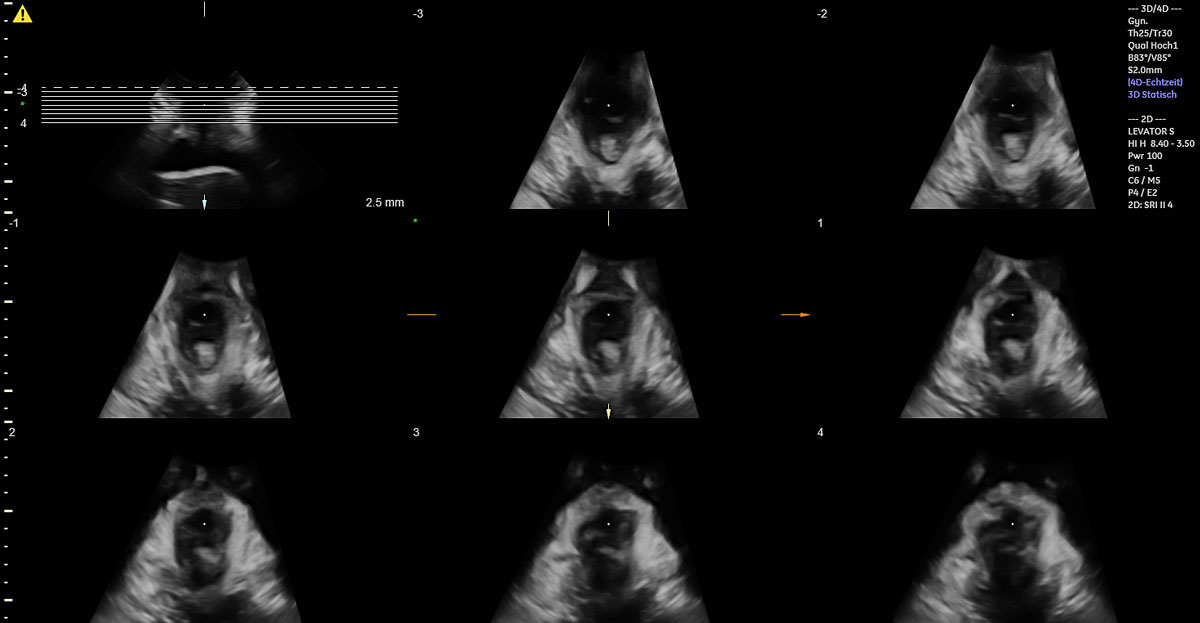

Of the 49 women with vacuum-assisted births in our cohort, 32 (65.3%) had an intact levator ani muscle, as shown in the illustration in fig. 2a and in the 3D ultrasound scan in fig. 2b. In contrast, 17 (34.7%) sustained levator ani muscle trauma, with 9 women (18.4%) having a partial levator ani muscle avulsion and 8 women (16.3%) having a complete levator ani muscle avulsion, as shown in the illustration in fig. 3a and in the 3D ultrasound scan in fig. 3b. No significant differences between the two groups were found, except for the state of their uterine contractions. Women without any levator ani muscle injury after vacuum extraction had more efficient uterine contractions compared to women with levator ani muscle trauma.

Figure 2b 3D translabial ultrasound image of an intact bilateral levator ani muscle.